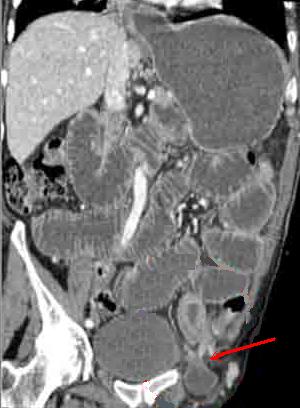

Boudin invagination

ileo-coecale du tumeur villeuse ( fleche rouge

) resoponsable une occlusion . Image TDM en coupe

axiale . |

| Image TDM en coupe axiale : Invagination

ileo- colique |

La vue coronale

de TDM montrant la cause de l'invagination : Lipome

du grele de grand diametre